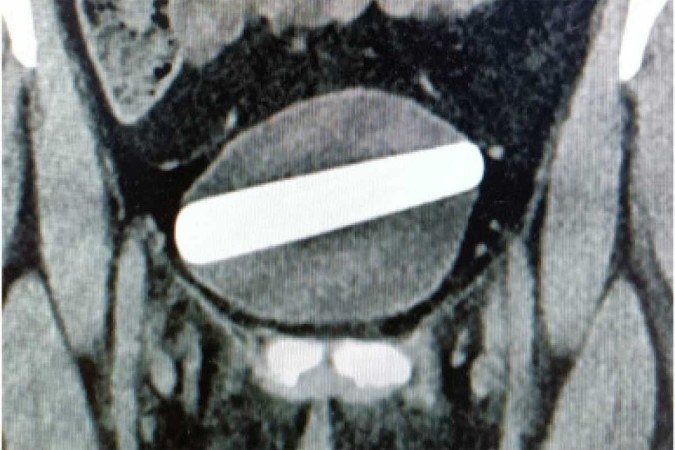

O objetivo, com cerca de 10 cm de comprimento e 2,5 de largura, ficou preso, horizontalmente, na bexiga da paciente

Uma mulher de 29 anos deu entrada na emergência de um hospital, em Israel, com queixas de disúria e desconforto abdominal, após ficar com um estimulador sexual feito de cristal preso, horizontalmente, na bexiga. O objetivo, com cerca de 10 cm de comprimento e 2,5 de largura, entrou na uretra durante uma relação sexual.

A mulher precisou ser anestesiada e passar por uma cirurgia, pois através de uma cistoscopia (usado para investigar patologias vesicais e uretrais), foi demonstrado que o objeto teria sido colocado de forma errada, horizontalmente, causando uma pressão local na parede lateral da bexiga.

Objeto de cristal retirado da bexiga da paciente

Com ajuda do cistoscópio, introduzido através da uretra, o objeto foi colocado na posição vertical e retirado cuidadosamente com uma pinça. A mulher recebeu alta horas depois do procedimento.